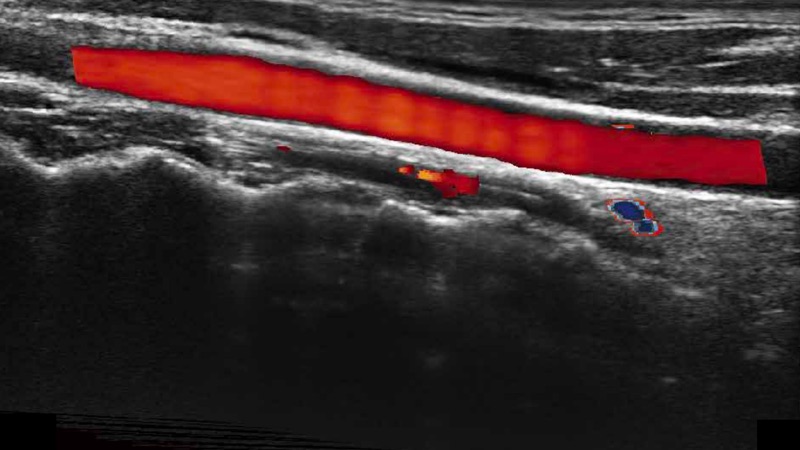

凸陣、線(xiàn)陣和相控陣探頭進(jìn)行實(shí)時(shí)掃描時(shí),開(kāi)啟擴(kuò)展成像模式,可以擴(kuò)展超聲圖像視野,以便更完整地查看大的病灶或組織器官的解剖結(jié)構(gòu)。

通過(guò)色彩血流和實(shí)時(shí)寬景相結(jié)合,可觀察到完整的靜脈或動(dòng)脈的血流,方便醫(yī)生檢查。實(shí)時(shí)掃查過(guò)程中,如有任何操作失誤也可以很容易地進(jìn)行回掃擦除,而不會(huì)中斷掃查。